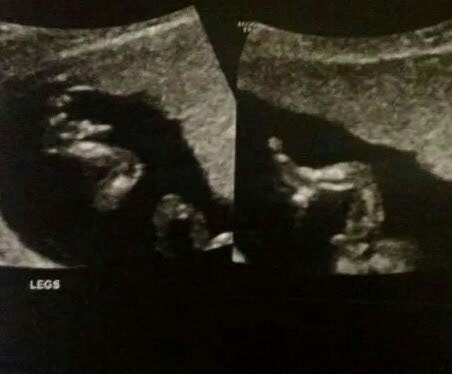

This scan was taken at 14weeks,

I find out the gender in 2weeks(:

What do you guys think?